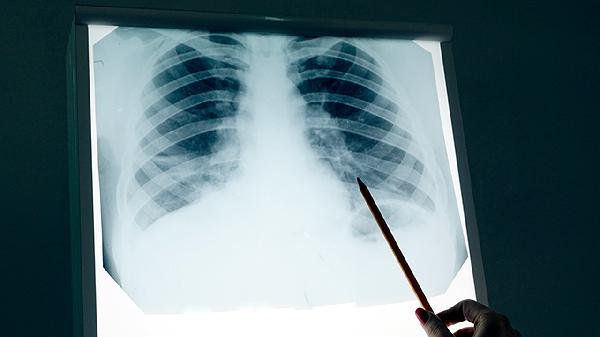

80岁肺癌中期患者生存期通常为1-3年,实际时间受到肿瘤分化程度、基础疾病控制、治疗耐受性、营养状态、心理因素等多方面影响。

控制高血压、糖尿病等基础疾病可减少并发症。心肺功能评估决定放疗耐受性,慢性阻塞性肺疾病会限制治疗选择。

立体定向放疗联合免疫治疗适用于不耐受手术者。化疗方案需根据肌酐清除率调整剂量,紫杉醇类较铂类更适合老年患者。